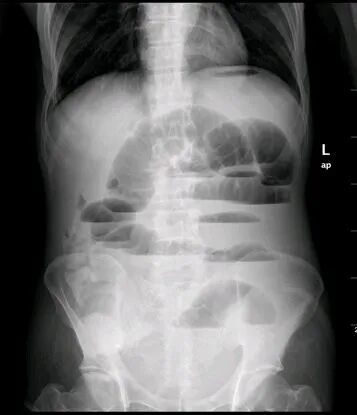

任何原因引起的肠内容物通过障碍统称肠梗阻。它是常见的外科急腹症之一。有时急性肠梗阻诊断困难,病情发展快,常致患者死亡。目前的死亡率一般为5%~10%,有绞窄性肠梗阻者为10%~20%。水、电解质与酸碱平衡失调,以及患者年龄大合并心肺功能不全等常为死亡原因。

弹簧征、液气平面、拱形肠管扩张